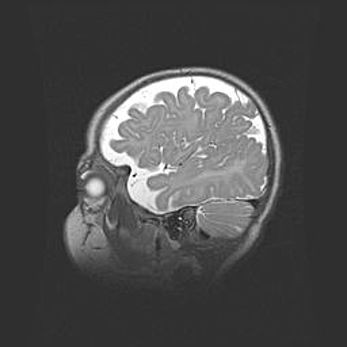

Наружная гидроцефалия с возможной атрофией височных областей.

Возраст: 28 дней

Вес: 3670 г

Пол: мужской

Окружность головы: 38 см

Срок гестации: 40 недель

Гидроцефалия головного мозга у новорожденных – это заболевание, которое характеризуется скоплением избыточного количества спинномозговой жидкости в желудочковой системе головного мозга в результате затруднения её перемещения от места выработки к месту поглощения в кровеносную систему или вследствие нарушения абсорбции. При открытой наружной форме гидроцефалии у новорожденных расширяются и переполняются субарахноидные пространства.

При нормотензивных  формах,  которые,  как  правило,  являются  следствием  перенесенных ишемических  повреждений  паренхимы  мозга,  возможно  сочетание микроцефалии  с нормотензивной гидроцефалией. В основе данных изменений лежит атрофия больших полушарий с преимущественной  локализацией  в  лобно-височных  областях.